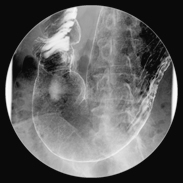

X線透視検査

X線を連続的に照射することで動画として確認することができ、画像としても保存できます。

内視鏡を使った胆管の拡張術や結石の除去、消化管(腸)の検査や治療に利用します。

当院では、従来型のTV装置とCアーム型の2台体制で、様々な検査・処置に対応しております。

また、予防医学センターでは、胃透視(バリウム)検査を多く行っています。